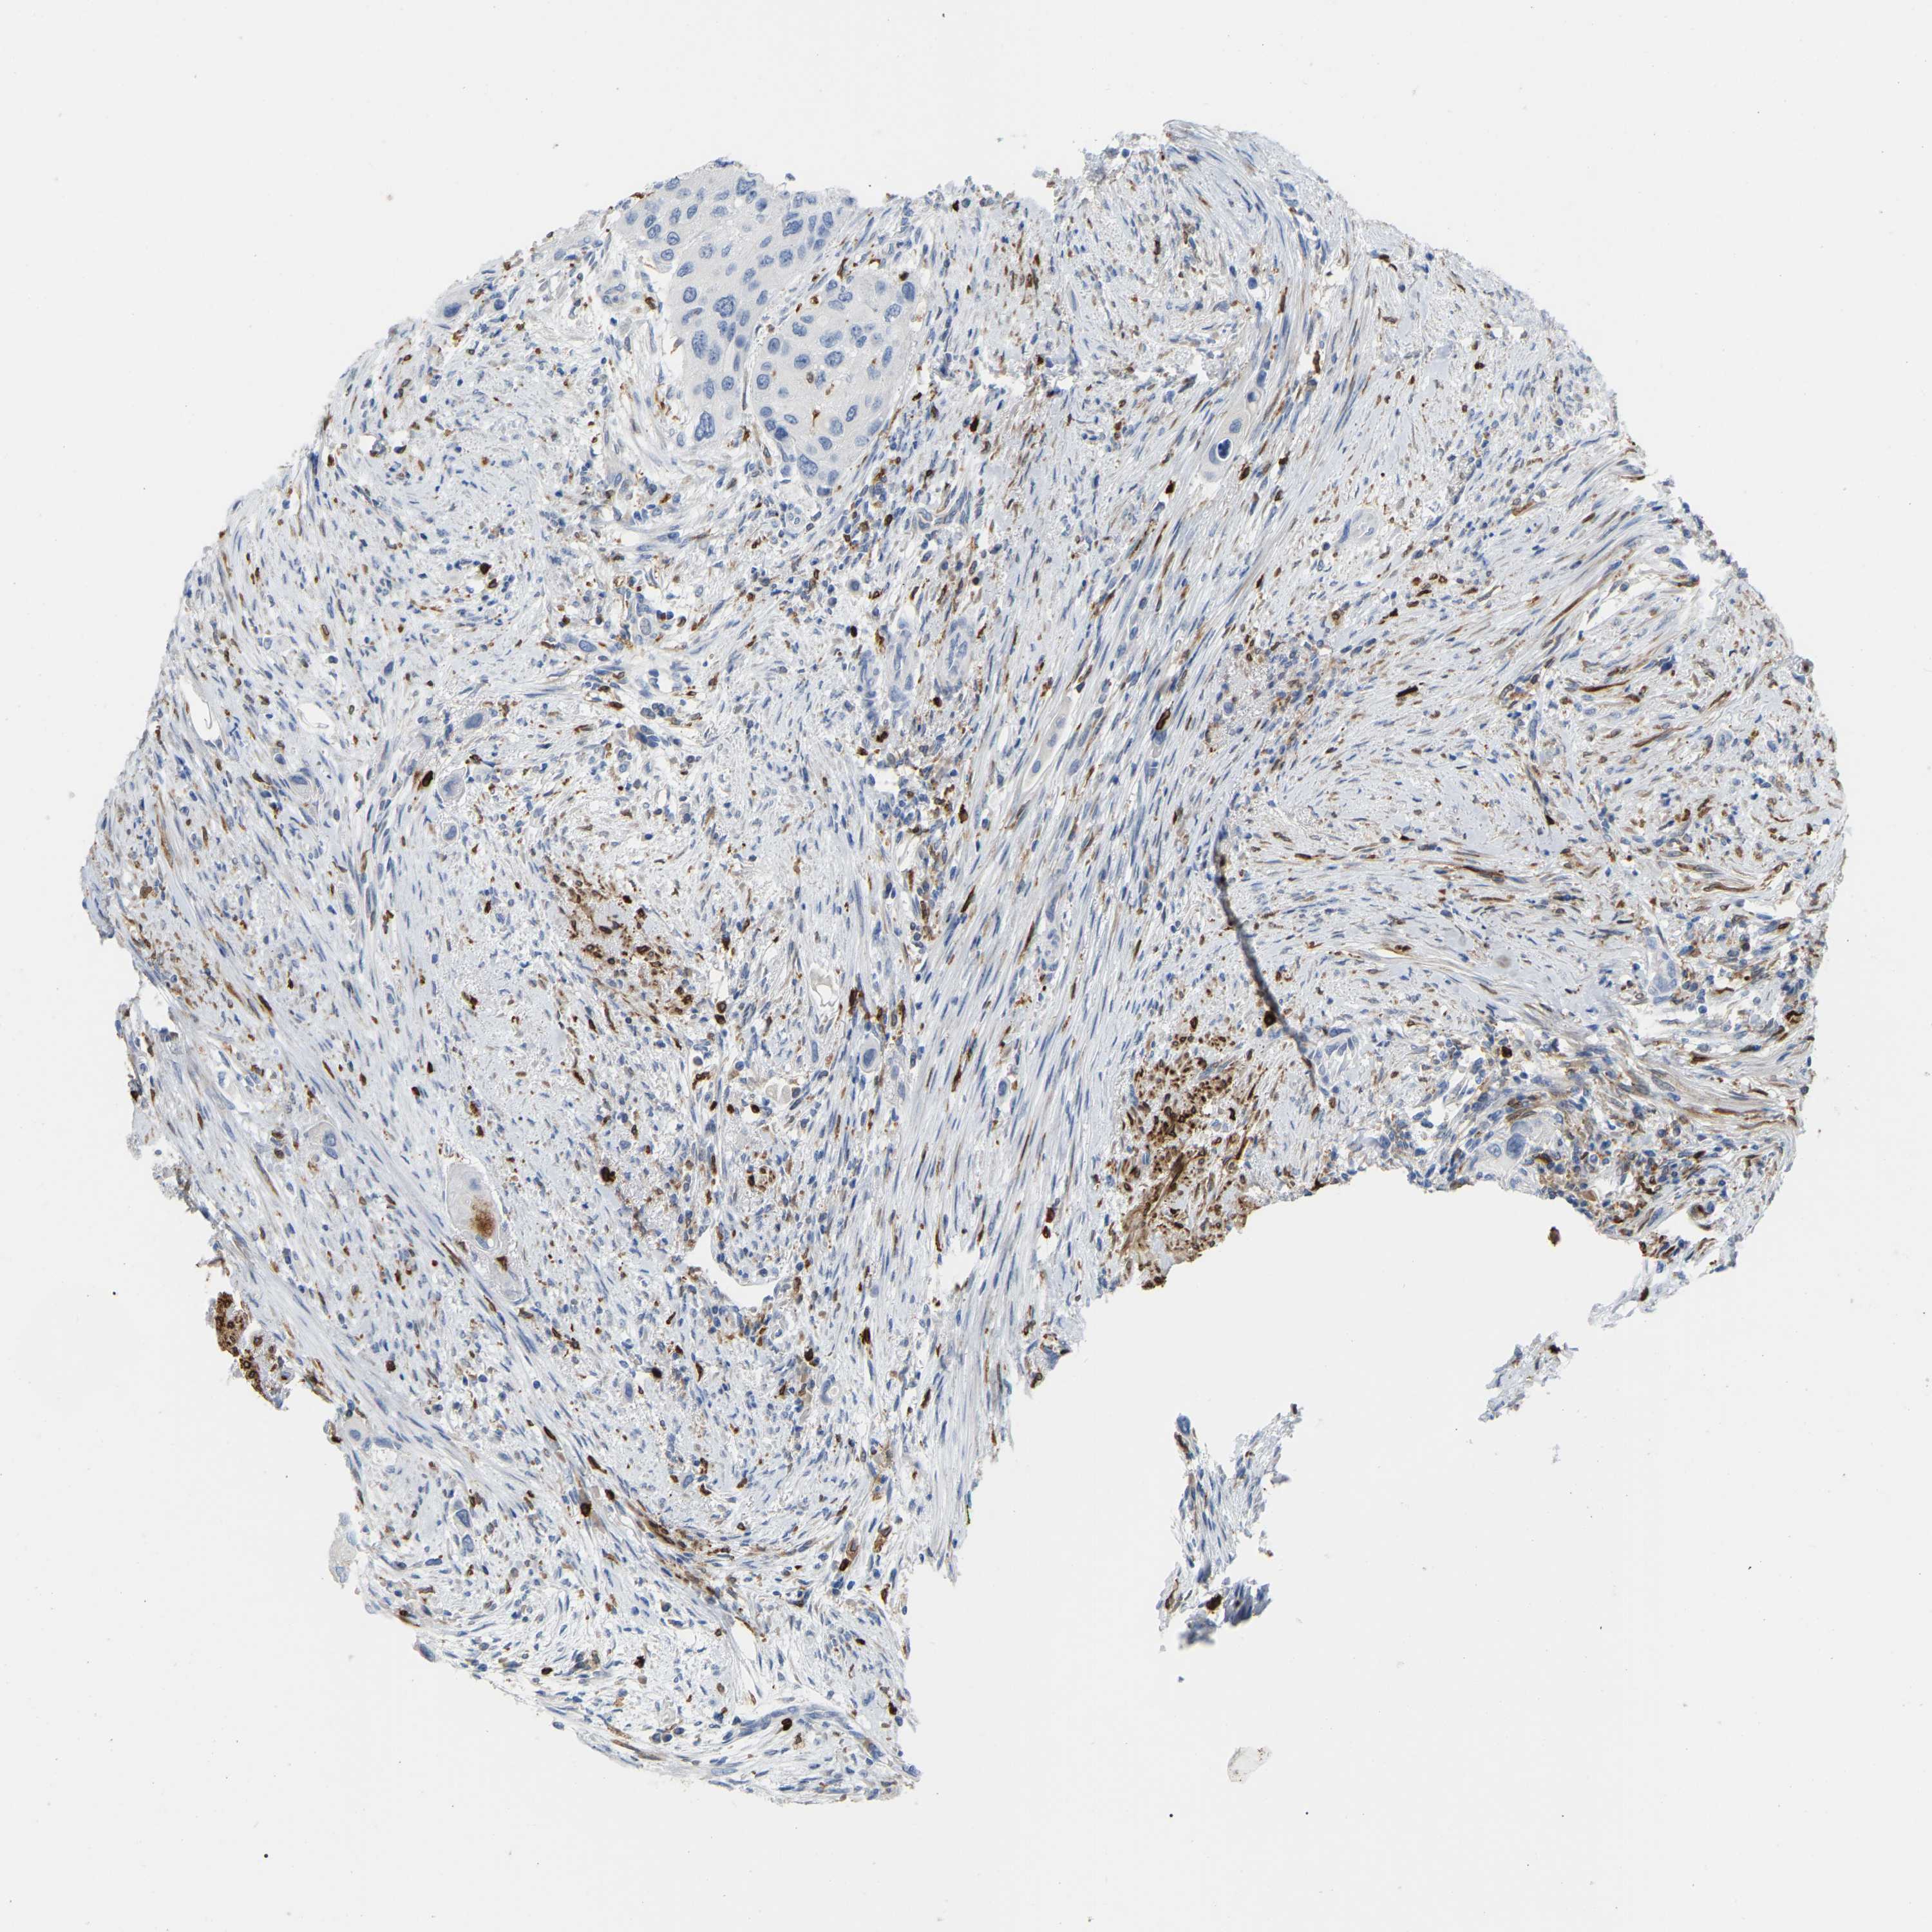

UROTHELIAL CANCER - Protein expressioni

A mouse-over function shows sample information and annotation data. Click on an image to view it in a full screen mode. Samples can be filtered based on level of antibody staining by selecting one or several of the following categories: high, medium, low and not detected. The assay and annotation is described here.

Note that samples used for immunohistochemistry by the Human Protein Atlas do not correspond to samples in the TCGA dataset.

Antibody stainingi

Antibody staining in the annotated cell types in the current human tissue is reported as not detected, low, medium, or high, based on conventional immunohistochemistry profiling in selected tissues. This score is based on the combination of the staining intensity and fraction of stained cells.

Each image is clickable and will lead to virtual microscopy that enables deeper exploration of all samples and also displays staining intensity scores, fraction scores and subcellular localization as well as patient and tissue information for each sample.

Antibody HPA002834

Antibody CAB020315

Urothelial carcinoma, High grade

Urothelial carcinoma, Low grade

Adenocarcinoma, NOS